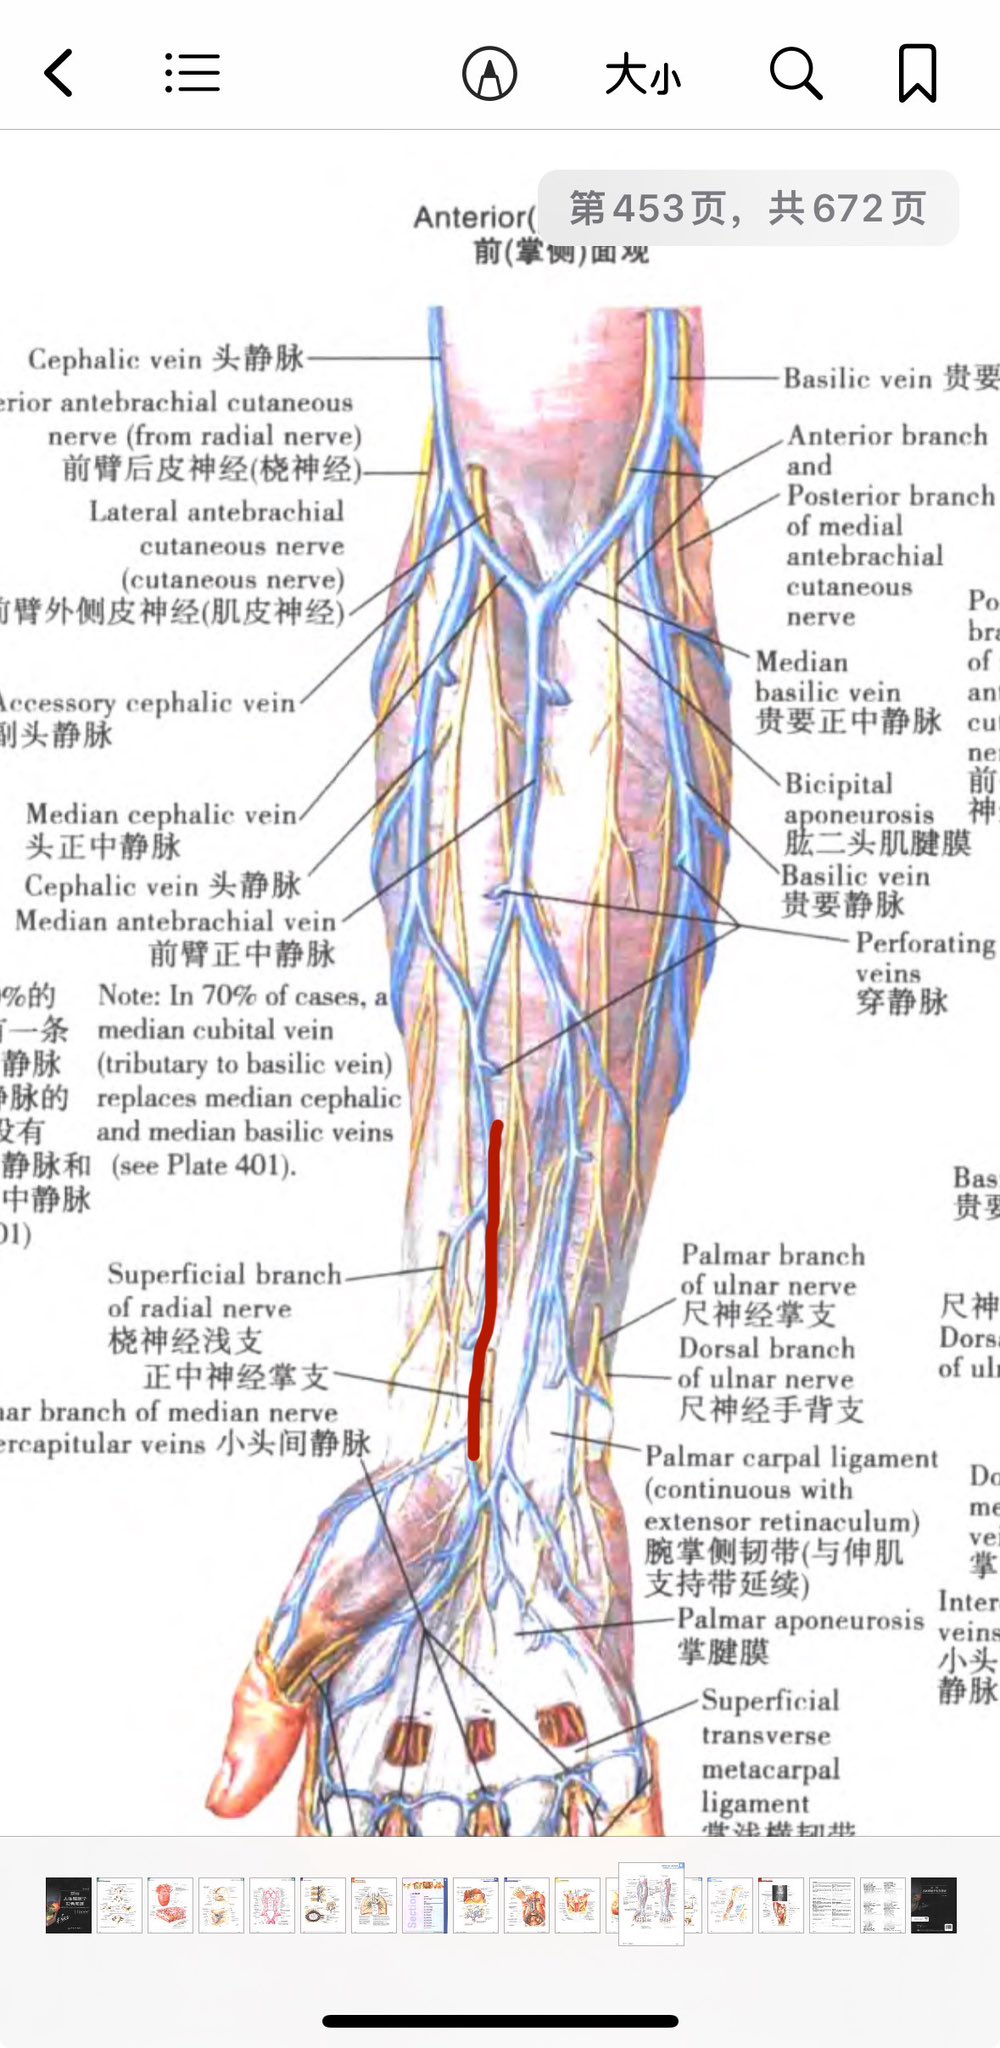

为什么中途换针头了呢,因为用那个软管输液针选择了错误的血管,太细了导致针头扎进血管回血了但可能有一半在管壁外,加上我没排干净空气,推进去一下子鼓包然后手腕肿了。。超痛。